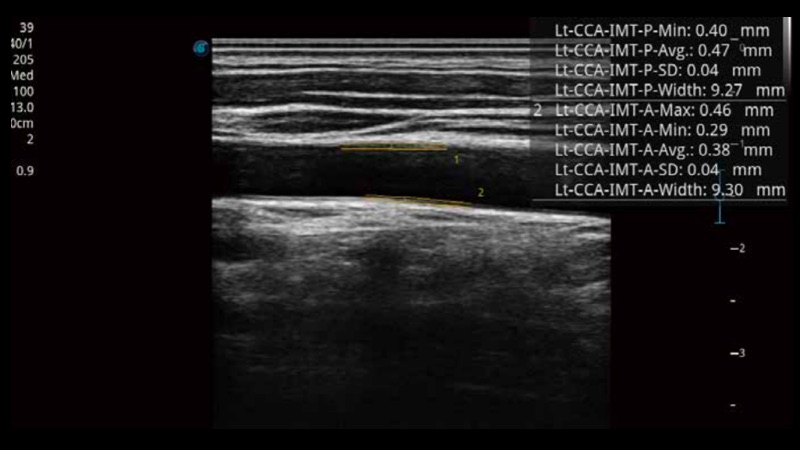

自動識別前后壁內(nèi)膜厚度,為心血管疾病早期評估提供快速準確依據(jù)。